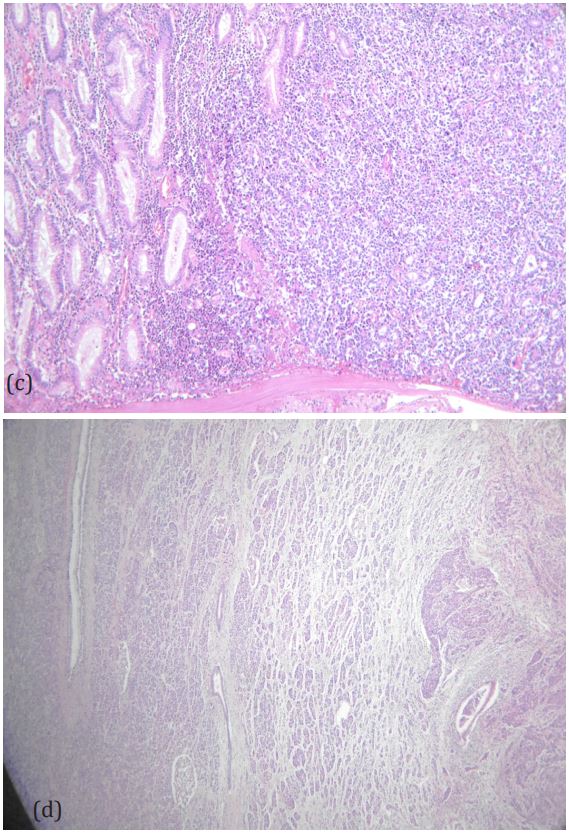

Figure 3b: H&E image of the primary gastric cancer

Figure 3c,d: Invasion of the gastric cancer to the transverse colon (c), pancreas (d).

Figure 3e: Cancer in the adhesional tissue on the surface of the spleen (red arrow).

An eighty-year-old woman presented with the symptoms of abdominal pain, slight fever of 37-38°C, and body weight loss. Upper Gastrointestinal (GI) examination performed one month prior to presentation revealed a gastric tumor, while Esophagogastroduodenoscopy (EGD) showed a type 3 tumor in the gastric fundus and corpus (Figure 1a). However, food residues covering the tumor surface prevented precise observation. Colonoscopy revealed an irregular surface elevation in the splenic flexure of the colon (Figure 1b), in which an adenocarcinoma was detected by biopsy. Contrast-enhanced computed tomography (eCT) revealed advanced GC with extensive invasion of the transverse colon, spleen, and pancreas (Figure 2a,b). Peritoneal dissemination and lymph node metastasis were suspected. The eCT image also showed gas in the pancreatic duct, indicating fistulation from the stomach to the pancreatic duct due to tumor invasion (Figure 2b). This fistula was presumed to be the cause of the patient’s low-grade fever. Thus, relatively rapid surgery was performed to control bacterial infection of the pancreatic duct and ensure resection of the advanced GC. Open surgery was performed, and extensive invasion of the GC into the pancreas and transverse to the descending colon was detected. Fortunately, no obvious peritoneal dissemination was observed. Therefore, a total gastrectomy with D2 lymphadenectomy combined with distal pancreatectomy, partial colectomy, and cholecystectomy was performed. Cholecystectomy was added as it is performed along with total gastrectomy as the standard procedure in our institute. The resected gastric tumor measured 160×80 mm (Figure 3a). Pathological tests revealed a poorly differentiated adenocarcinoma of the stomach invading the pancreas, transverse colon, and splenic serosa (Figure 3b-e). No metastasis was identified in the dissected lymph nodes or peritoneum. The pathological cancer stage was IIIA, according to both the TNM Classification of Malignant Tumours-8th edition [13] and the 15th edition of the Japanese Classification of Gastric Carcinoma[14]. Approximately two months after surgery, we initiated adjuvant chemotherapy with tegafur/gimeracil/oteracil, which was discontinued after only two months due to severe adverse events. Two years after surgery, the patient remains alive without relapse.